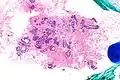

Very low magnification micrograph of atypical ductal hyperplasia (ADH). The piece with ADH was circled by the pathologist with a marker, as it is so small, and sent for an additional opinion. H&E stain.